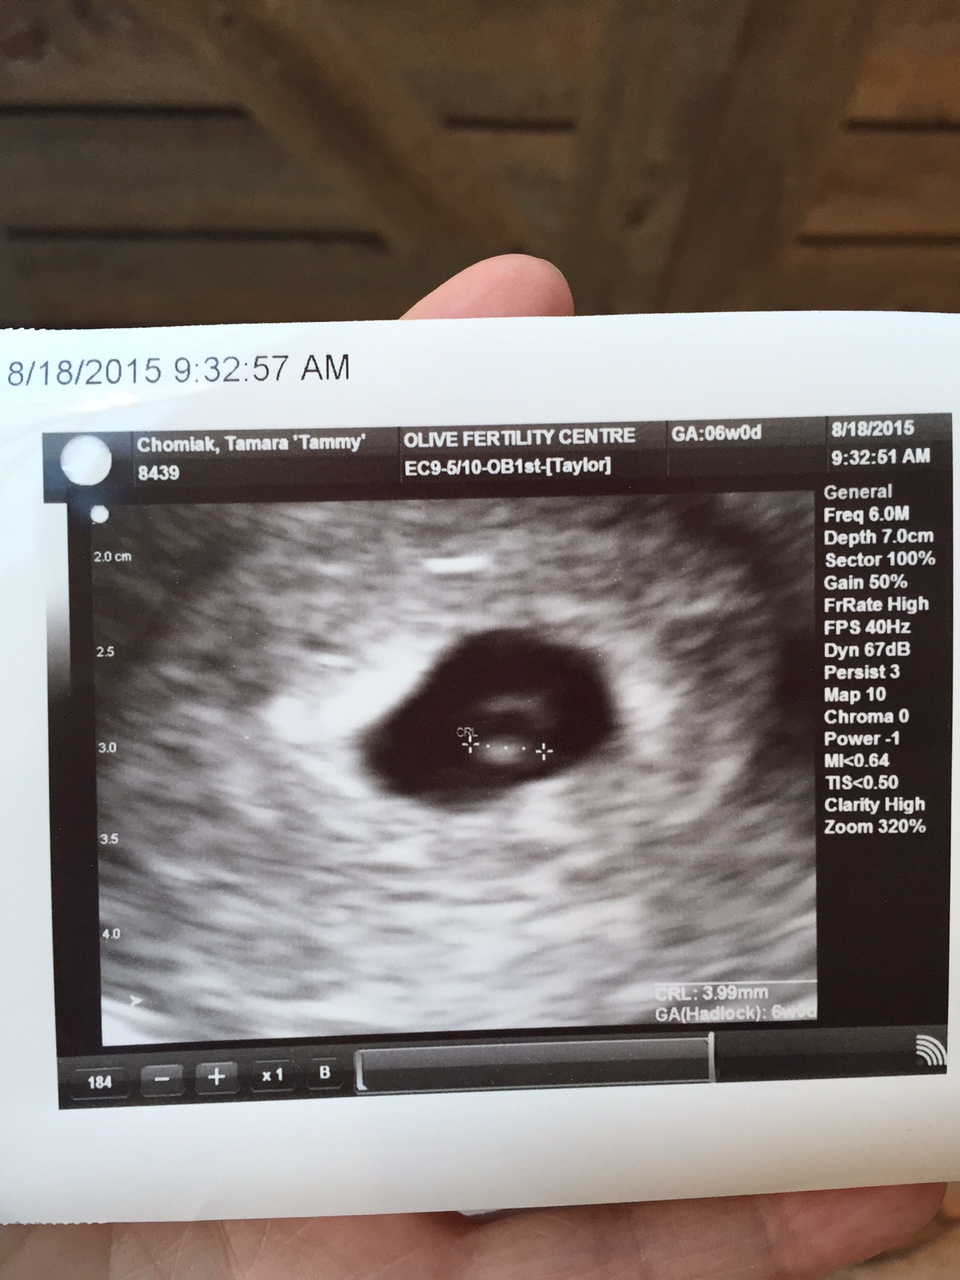

6 week ultrasound: